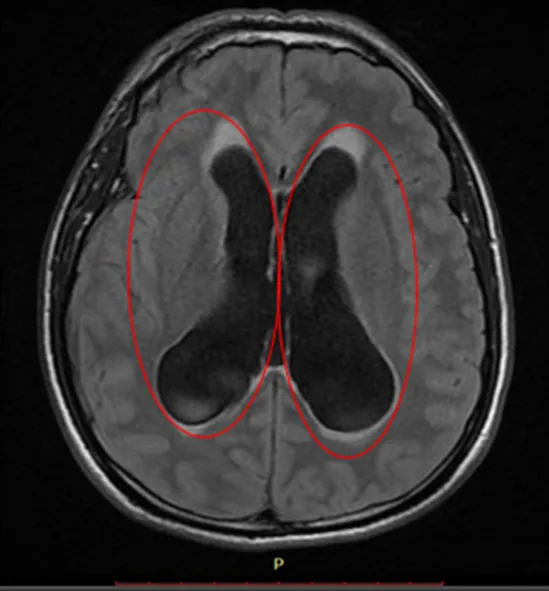

Resonancia Magnética Cerebral Simple

Hallazgo en RNM Cerebral

A nivel de brazo anterior de capsula interna derecha se observa pequeña área con cambios de intensidad de la señal de comportamiento magnético isointenso en T1 con respecto a la sustancia gris, e hiperintenso en T2 con restricción hídrica en difusión, mide 6.0 mm x 5.0 mm en sus mayores ejes sin repercusión sobre estructuras adyacentes.

Se observa dilatación simétrica en ventrículos laterales así como de tercer y cuarto ventrículo, este último provocando desplazamiento de mesencéfalo y parénquima cerebeloso en sentido anterior y posterior respectivamente, asociada a hiperintensidad moderada de la sustancia blanca periventricular en secuencia FLAIR en relación con edema intersticial.